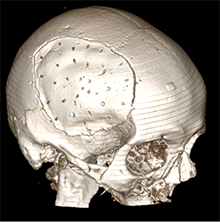

53 m. vyras sumuštas gatvėje ir greitosios medicinos pagalbos atvežtas į Priėmimo skyrių. Pacientui atlikta galvos kompiuterinė tomografija (GKT). Rasta: poūmė, stora, apie 16 mm dydžio subdurinė hematoma (SDH) dešinėje pusėje konveksitaliai ir ūmi nedidelė SDH kairėje pusėje frontoparietaliai. Vidurio struktūrų dislokacija (VSD) į kairę – minimali. Kairėje – kaukolės skliauto linijinis lūžis. Nustatyta nosies kaulų, nosies pertvaros, dešiniojo viršutinio žandikaulio kaktinės ataugos ir kūno, sinuso sienelių lūžių, dešinės akiduobės medialinio krašto lūžių ir dešiniojo skruostinio lanko lūžių (1 pav.). 2020 m. liepos mėn. pacientas skubos tvarka operuotas: atlikta dešinė kraniotomija, pašalinta hematoma. Atlikus kontrolinę GKT, buvo matyti, kad pašalinta didžioji hematomos dalis (2 pav.). Pacientas konsultuotas veido ir žandikaulio chirurgo, skubus chirurginis gydymas neindikuotas. Praėjus 3 savaitėms, pacientas, esant gerai funkcinei ir neurologinei būklei, tolesnio gydymo perkeltas į slaugos ligoninę, vėliau išleistas gydytis ambulatoriškai.

1 pav. Prieš pirmąją operaciją (poūmė, stambi, iki 16 mm SDH apie dešinįjį pusrutulį, ūmi nedidelė SDH kairėje F-P; VSD į kairę ~3 mm)